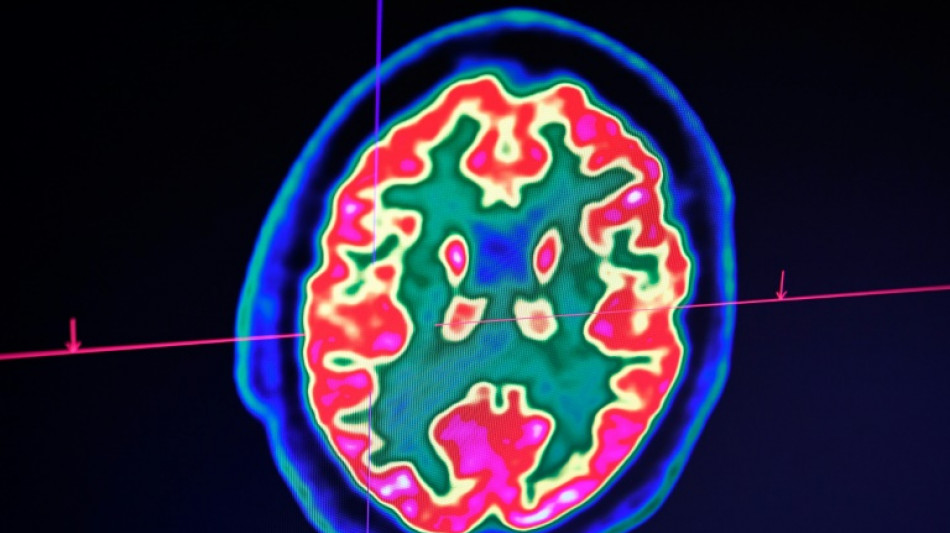

Cancer du cerveau: la guérison d'un enfant ouvre de grands espoirs pour la recherche / Photo: Fred TANNEAU - AFP